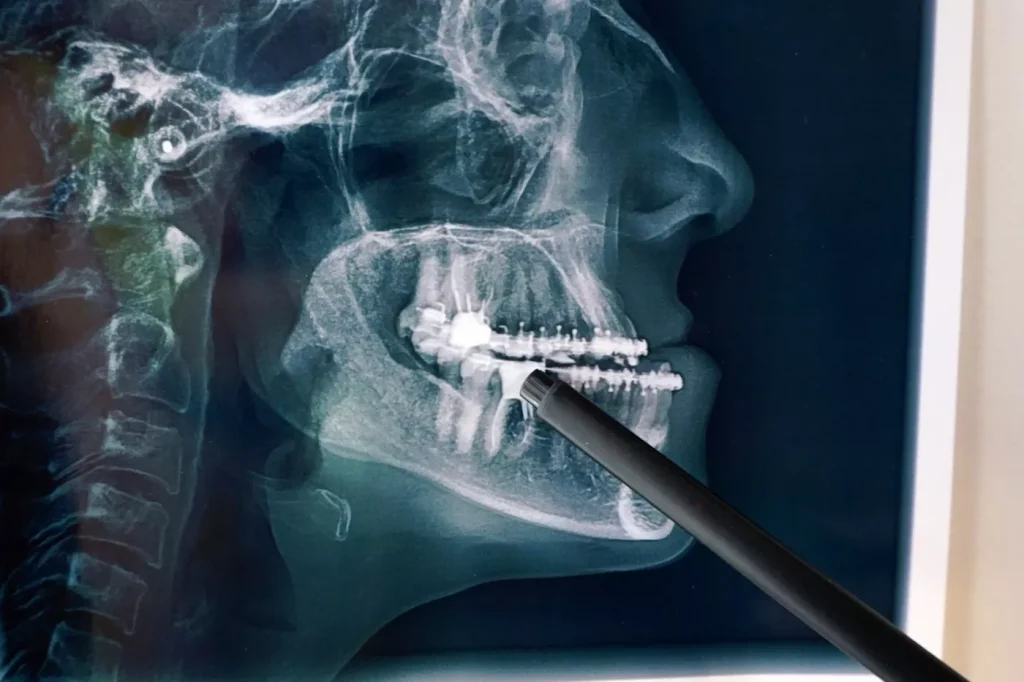

Tehnica de radiologie dentară utilizează raze X pentru obținerea unor imagini ale zonelor invizibile ochiului uman.

Obținerea acestor imagini este posibilă datorită faptului că țesuturile dure și mineralizate ale dinților blochează o parte din radiații. Acest lucru permite zonelor puternic mineralizate să pară mai deschise la culoare.

Pe o radiografie, un dentist poate discerne, în acest mod, între smalțul sau învelișul exterior al dintelui, stratul de dentină subiacent și camera pulpară ce protejează țesutul nervos ce hrănește dintele.

Zonele cu infecție, cu țesut osos afectat, cariat, fiind demineralizate, apar mai întunecate, semnalizând probleme.

Radiografiile panoramice digitale sunt proiectate pentru a surprinde ambele arcade ale pacientului într-o singură imagine. Multe dintre cele mai noi tehnologii oferă softuri pentru interpretarea, prelucrarea tomografiilor dentare și pentru alte nevoi de imagistică specializate.

Tomografiile cu fascicul conic sunt cel mai frecvent asociate cu planificarea tratamentului implantului dentar, dar aceste sisteme puternice de imagistică 3D schimbă decisiv modul în care echipa medicală a clinicii se ocupă de ortodonție, endodonție și o serie de alte situații clinice.